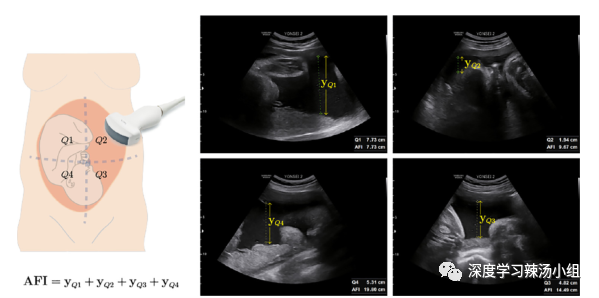

1.AFI测量:AFI是超声图像各象限羊水最深深度之和。这里,Q1、Q2、Q3、Q4分别表示各象限,yQ1、yQ2、yQ3、yQ4分别表示各象限的羊水最深深度(图1)。

图1:AFI测量过程